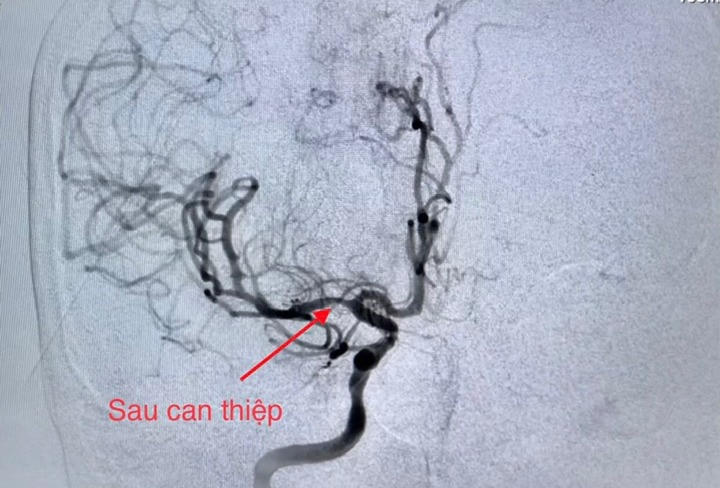

Mạch vành tái thông tốt sau can thiệp |

Ê-kíp can thiệp tim mạch trong thời gian khoảng 40 phút đã hoàn tất nong động mạch vành bị tắc và tiến hành đặt giá đỡ (stent), giúp tái lập dòng máu nuôi tim. Ngay sau đó ê-kíp can thiệp mạch não chụp kiểm tra phát hiện tắc động mạch não giữa bên phải; thủ thuật lấy huyết khối tái thông mạch máu bị tắc với thời gian 20 phút.